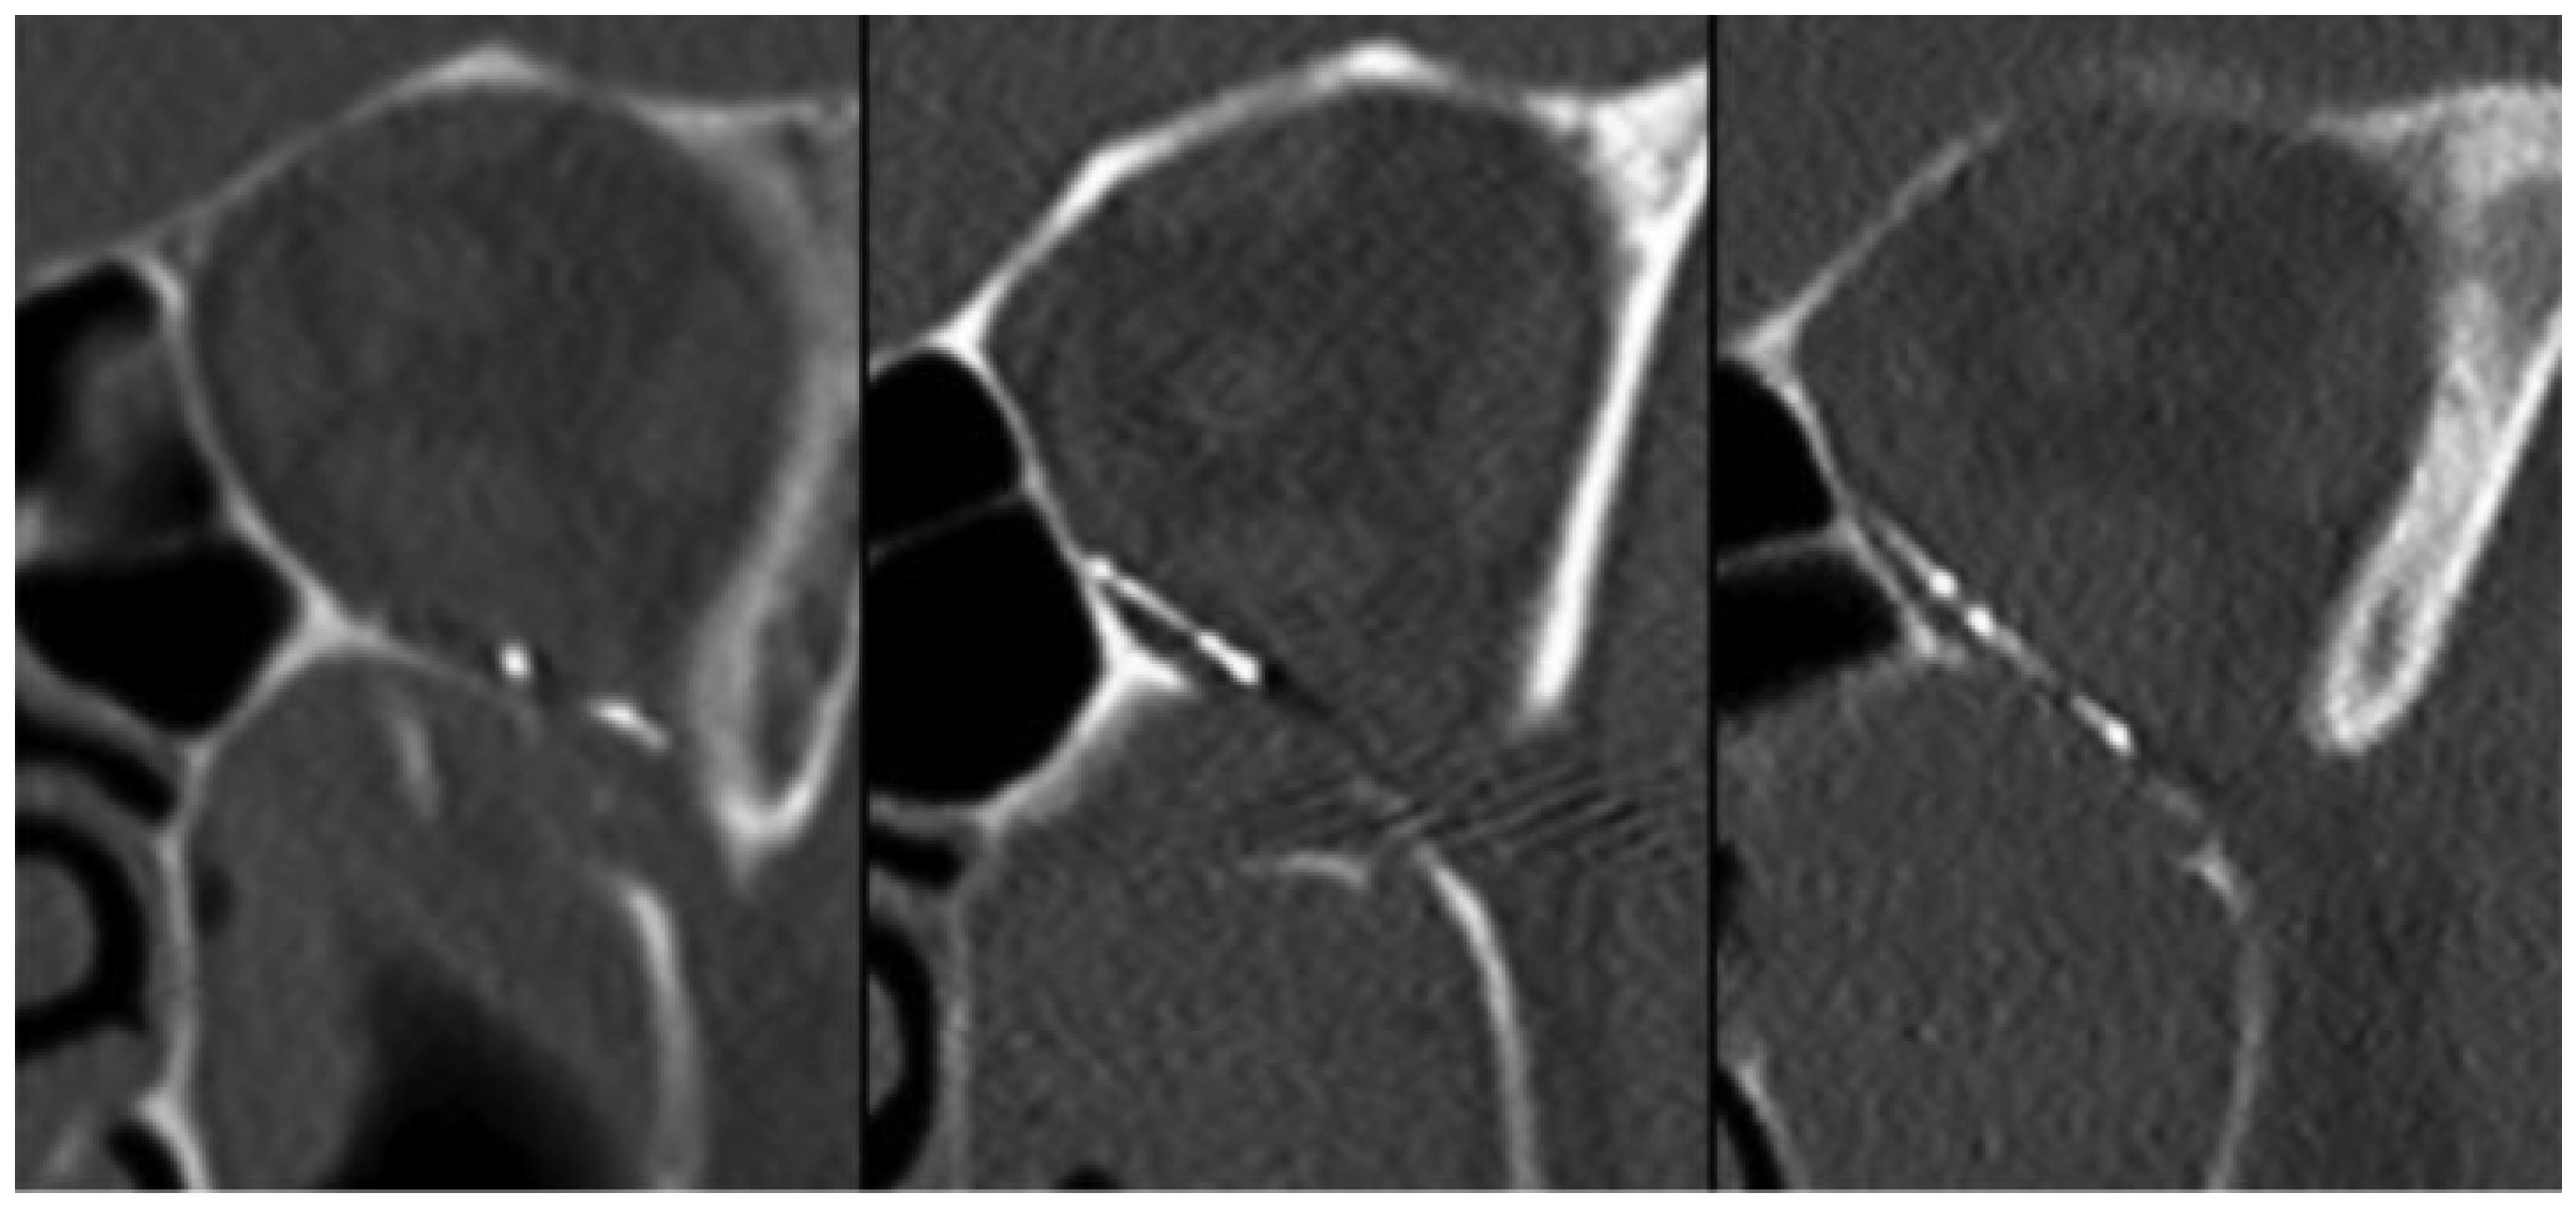

Limitations of this study include a retrospective review methodology. Due to practical limitations, we were unable to assess all available implants and instead opted to focus on the most commonly used mesh and non-mesh products in our practice. We sought to reduce any possibility of selection bias by randomizing case selection for analysis. Nevertheless, this was not a randomized control trial and, as such, a significant difference in the prevalence of medial wall fractures was seen based on which implant material was used. It is possible that there is a difference in the amount of bleeding in cases with medial wall fractures or even that some of the ethmoid sinus air cells can act as an additional reservoir for bleeding. Our study is based on individual postoperative CT scans, as it is not possible to directly visualize the passage of blood into the maxillary sinus and we did not directly measure drain output. Patients with excessive orbital hemorrhage with blood accumulation were not included in this study because these events are rare and such patients receive emergent hemorrhage evacuation before any CT imaging of the maxillary sinuses can be acquired. This study was not able to account for fracture size, but given that all patients met criteria for repair, all fractures were likely substantial. Postoperative fracture coverage is also difficult to assess. It is standard practice to extend the implant posteriorly to the palatine bone; however, a small portion of the posterolateral defect near the inferior orbital fissure or groove can sometimes remain uncovered (Figure 4) and may be too small to visualize reliably on postoperative imaging. We did not compare sinus filling between pre and postoperative imaging because blood was evacuated from the maxillary sinus at the onset of surgery and because most preoperative images were taken days or weeks before the operation. Data from multiple surgeons were included in this study, and both drain placement and implant material were selected based on surgeon preference, which is another limitation of this study.

Figure 4. Coronal CT imaging demonstrating variability of posterior implant configuration in three patients receiving porous polyethylene-coated titanium implants. Despite placement on the palatine bone medially, a small portion of the posterolateral defect near the inferior orbital fissure or groove often remains uncovered as best seen in the center image.